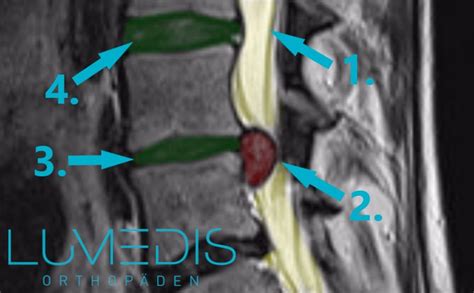

Epidurale interlaminäre Infiltration: Ein Bandscheibenvorfall (blaue Ausbuchtung) demonstriert die Einengung des Spinalkanales mit Verdrängung der Nervenwurzeln. Die lokale Entzündung ist rot markiert. Die Spitze einer Hohlnadel wird von hinten zwischen 2 Dornfortsätzen der Wirbelkörper in den Kanal vorgeschoben, ohne die Hirnhäute zu durchstechen.